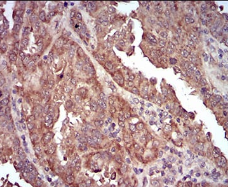

IHC    1/200 - 1/1000